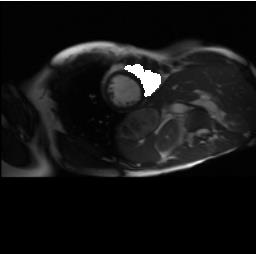

2D biomedical semantic segmentation is important for robotic vision in surgery. Segmentation methods based on Deep Convolutional Neural Network (DCNN) can out-perform conventional methods in terms of both accuracy and levels of automation. One common issue in training a DCNN for biomedical semantic segmentation is the internal covariate shift where the training of convolutional kernels is encumbered by the distribution change of input features, hence both the training speed and performance are decreased. Batch Normalization (BN) is the first proposed method for addressing internal covariate shift and is widely used. Instance Normalization (IN) and Layer Normalization (LN) have also been proposed. Group Normalization (GN) is proposed more recently and has not yet been applied to 2D biomedical semantic segmentation, however, no specific validations on GN were given. Most DCNNs for biomedical semantic segmentation adopt BN as the normalization method by default, without reviewing its performance. In this paper, four normalization methods - BN, IN, LN and GN are compared in details, specifically for 2D biomedical semantic segmentation. U-Net is adopted as the basic DCNN structure. Three datasets regarding the Right Ventricle (RV), aorta, and Left Ventricle (LV) are used for the validation. The results show that detailed subdivision of the feature map, i.e. GN with a large group number or IN, achieves higher accuracy. This accuracy improvement mainly comes from better model generalization. Codes are uploaded and maintained at Xiao-Yun Zhou's Github.